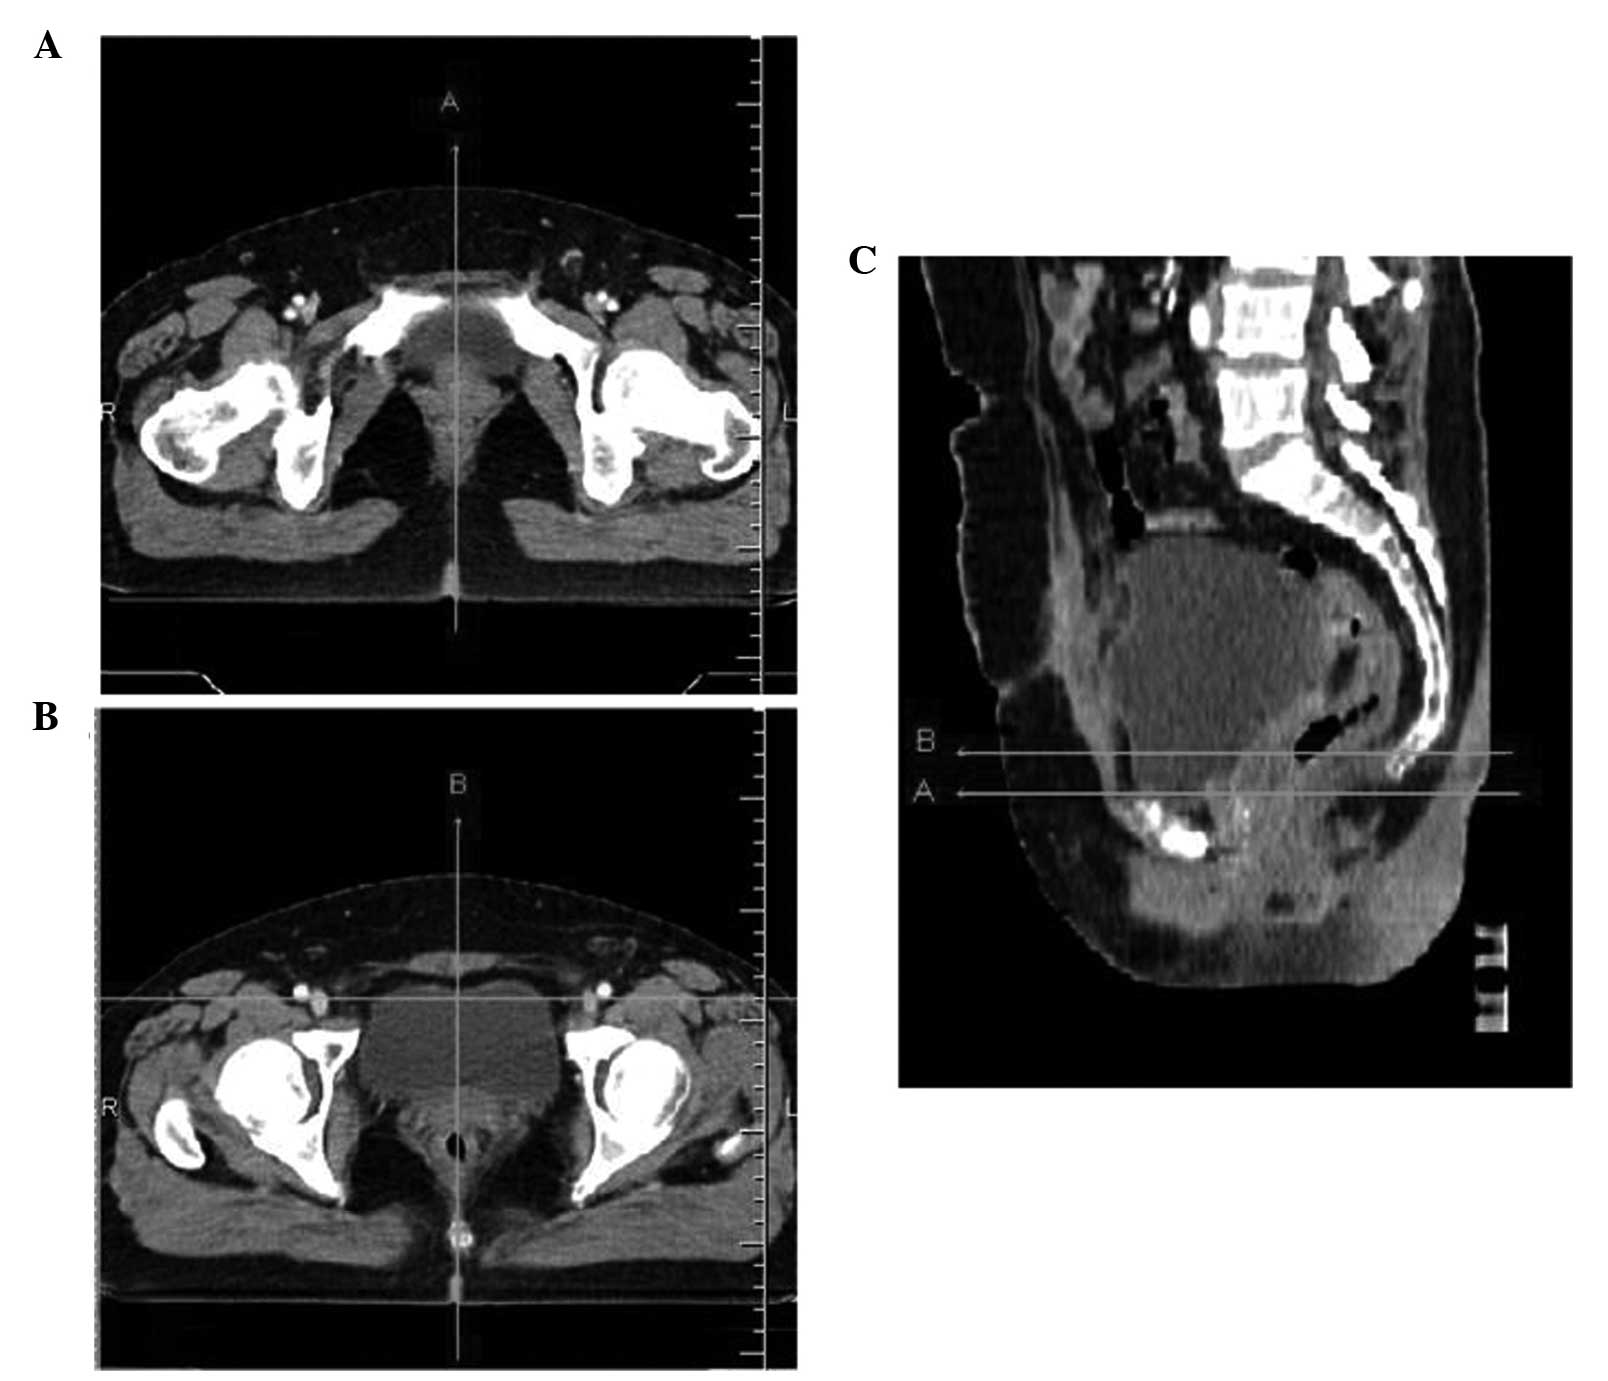

Interfractional variations of the bladder, rectum and vagina may affect the accuracy of postoperative intensity‑modulated radiotherapy in patients with cervical cancer. This study aimed to assess the interfractional variations with daily kv cone‑beam computed tomography (CBCT). All the patients were instructed to control the filling status of the bladder and rectum. CBCT images were obtained daily after set‑up and the bladder, rectum and vagina were contoured on each CBCT scan. All the contours were transferred to the planning CT following image fusion. Interfractional variations in pelvic organs were assessed with CBCT based on two reference lines, which were identified as A (the midsaggital line across the superior border of pubic symphysis) and B (a parallel line 1.5 cm above line A). The mean volume (range) of the bladder and rectum was 156.5 (1.7‑626.5) and 48.2 (11.3‑139.7) ml, respectively. The uniform planning target volume (PTV) margin of 10 mm failed to encompass the vagina in 17.3 and 18.1% of the fractions on lines A and B, respectively. The motion of the vagina (standard deviation) was 0.3 (0.3) and 0.1 (0.5) cm on lines A and B, respectively. The anteroposterior dimension and position of the vagina were significantly affected by the filling status of the bladder (P<0.05), but not by that of the rectum. Although instructions were given, the interfractional variations of the vagina and other pelvic organs were significant, which may exceed the uniform PTV margin; therefore, more effective methods to decrease these variations should be investigated.